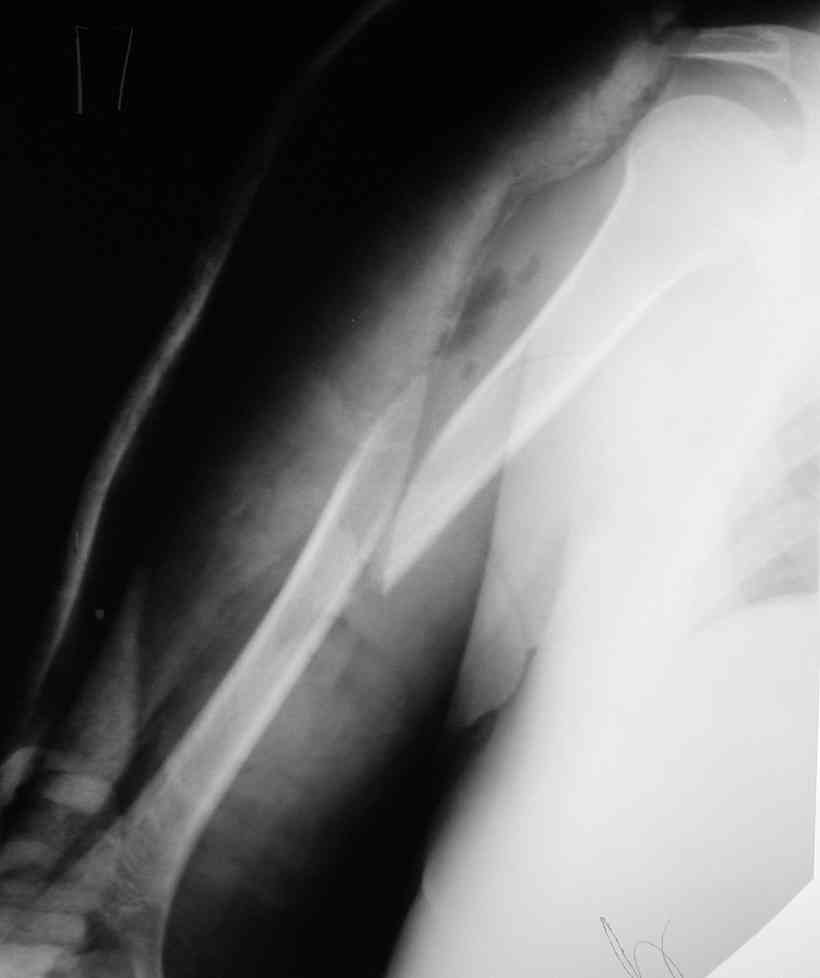

Такие надмыщелковые переломы в изолированном виде у нас в последние годы обычно фиксируются плоским титановым стержнем a la Зверев-Ключевский антеградно. Но тут еще и вышележащие проблемы.

Наверно, можно пойти на укорочение, убрав металлический цилиндр, не такой уж большой дефект. Снимки в чем-то похожего пациента прилагаю - тоже несращение диафиза после многократных операций, и надмыщелковый свежий перелом (случился после удаления обломка стержня аппарата).